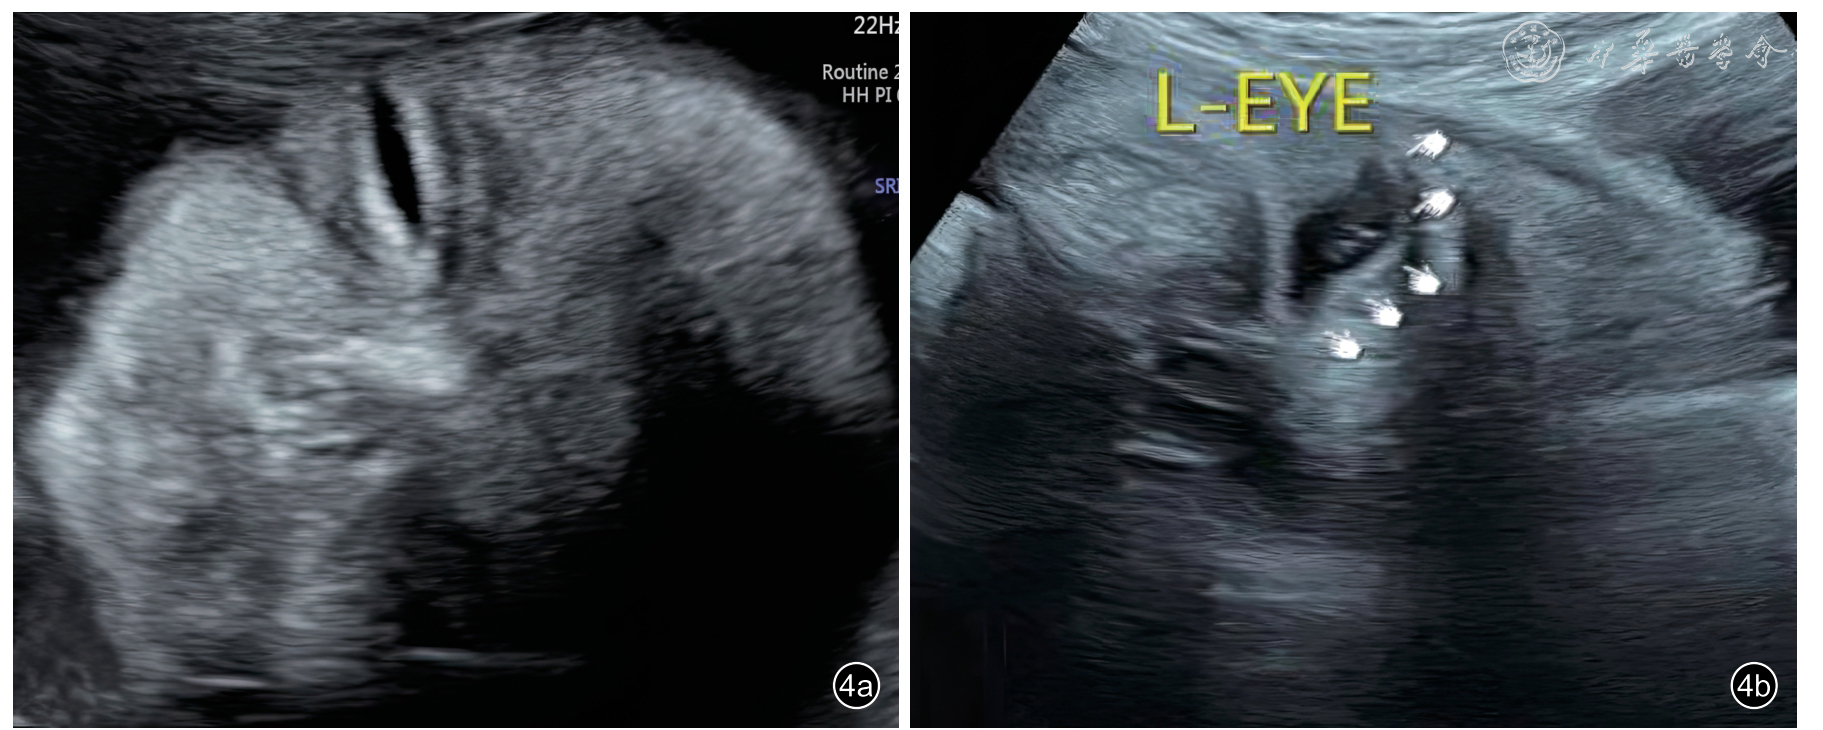

正常胎儿睑裂的产前超声表现有3种:呈线状高回声(图2)、线状低回声(图3)、带状无回声(图4)。孕20周前,10例(100%)胎儿睑裂均呈线状高回声;妊娠20+1~28周,睑裂主要表现为线状高回声,呈线状低回声和带状无回声者占比较低;妊娠28周后,睑裂呈线状高回声的比例明显减低,主要表现为线状低回声,少部分可以表现为带状无回声。胎儿睑裂产前超声表现在冠状切面和经眼睑中部矢状切面表现一致(表2)。

图4 胎儿睑裂的带状或小叶片状无回声表现。孕39+3周胎儿左眼(L-EYE)眼睑冠状切面超声图像表现为睁眼时睑裂的不同状态,图a呈眼睛微微睁开的细带状无回声,测得睑裂宽约2.5 mm,图b为眼睛完全睁开的状态,测得睑裂宽约8.2 mm